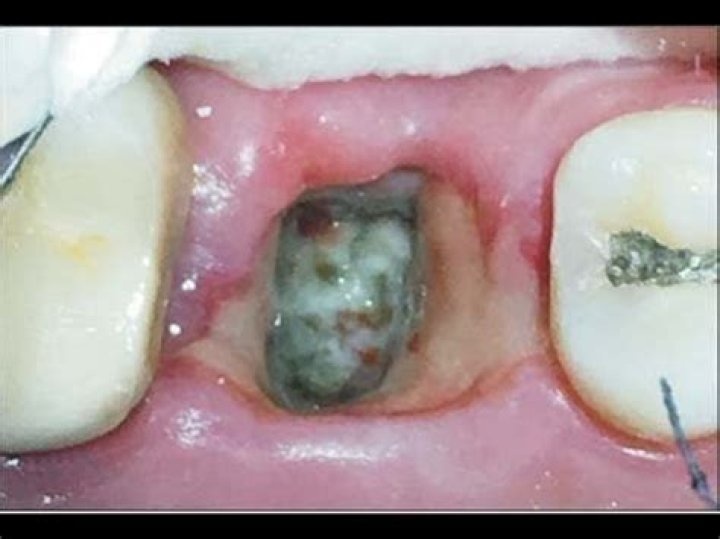

What color is dry socket?

A dry socket appears as an empty hole in the place of the removed tooth. The exposed bone is visible from the socket. The opening may look dry and have a creamy white color, just like a bone.

Is dry socket GREY?

You may have dry socket if: You can see a visible bone in the socket, or your socket appears grey in appearance or empty-looking. You're in severe pain following your tooth extraction. This pain will radiate from the extraction site to your ears, eyes or temples.

What does a dry socket look like vs normal?

If you can visibly see your extraction site, you may see a few visible signs if you have a dry socket. A healthy socket will be a hole with a noticeable blot clot in the center. If your socket appears white in color, chances are you are seeing exposed bone and have lost the blood clot.